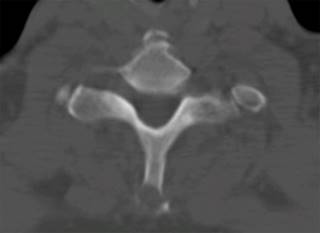

El paciente aporta una tomografía axial computarizada (TAC) y una resonancia magnética nuclear (RMN) (Figuras 1 y 2) que muestran una lesión lítica inespecífica en la espinosa de T1 y otra lesión en el cuerpo vertebral de L2. Ante estos hallazgos, se solicita una gammagrafía y una TAC toracoabdominal y se reprograma al paciente en una semana en consultas. Se realiza la gammagrafía que sólo muestra captación a nivel de ambas lesiones vertebrales. La TAC toracoabdominal informa de un enfisema paraseptal con atelectasias en el lóbulo inferior derecho y un área inespecífica en vidrio deslustrado en el lóbulo medio, sin alteraciones en el parénquima pulmonar ni otras lesiones a nivel abdominal.

Figura 1: Tomografía axial computarizada (TAC) axial que muestra lesión lítica en apófisis espinosa de T1.